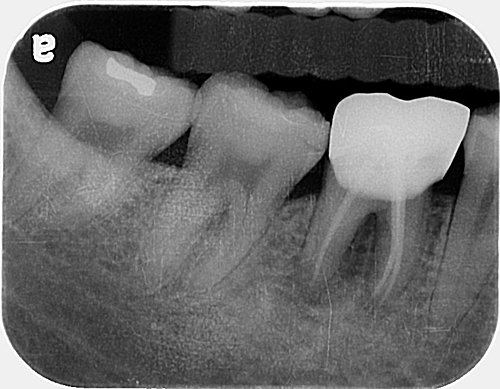

D小姐 右下大牙 常常腫起來 長膿包 有時兩三天自己會消掉 隔一陣子又腫起來....

由X光片可見 兩個牙根之間的骨頭 已遭破壞吸收 所以細菌會深入牙根之間 刷牙也刷不到

所以會常常腫起來 並持續破壞骨頭 造成牙齒搖動 ~